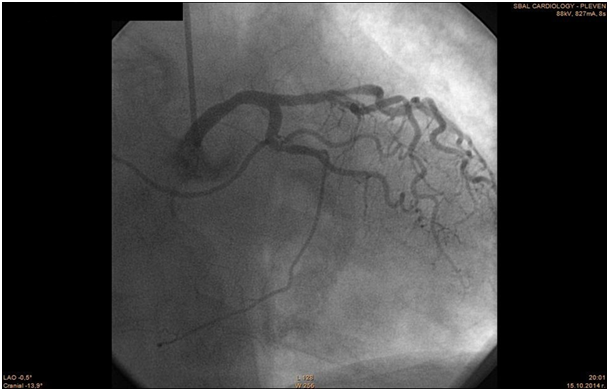

The patient was transferred to the Catheterization Laboratory in order to undergo coronary angiography. The coronary angiography revealed normal anatomy of Left Main Coronary Artery, LAD- 80% mid segment stenosis. LCx - irregularities. RCA - anomalous origin from the left Valsalva sinus. 50% mid segment stenosis, distal occlusion with thrombus. PCI was performed with guiding catheter XB 3.5 6F, coronary guide wire Terumo Runthrough 0.014". Predilation with balloon 2, 75/20 mm and implantation of two drug eluting stents 2, 75/28 mm with overlapping. Post-dilation at the site of overlapping with the balloon of the second stent.

The patient was previously hospitalized for chronic heart failure NYHA class III and ventricular fibrillation, which was treated with a synchronized shock. She also has arterial hypertension present for the past 20 years, permanent atrial fibrillation and type 2 diabetes. For these conditions she was on the following medication therapy: Bisoprolol Fumarate, Telmisartan, Amiodarone, Gliclazide, Metformin, Acenocoumarol, Tavipec and Azithromycin (Figure 46). The cause of the present ischemia is not a result of a mechanical compression of the artery, but is a result of atherosclerosis and plaque rupture with subsequent development of myocardial infarction (Figure 7 & 8).

Figure 5 LCA & RCA.